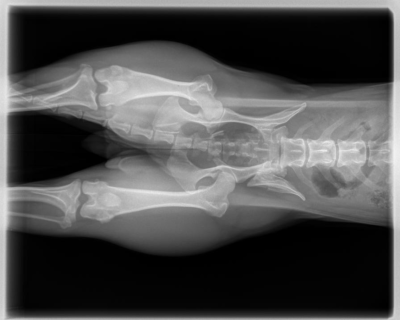

Upon arrival, it was obvious that Lily Bean was in serious pain. She could not put any weight on her left rear leg, and her movement was severely limited. Shelter staff rushed her to an emergency veterinary clinic where x-rays revealed two puncture wounds and a fractured pelvis. Her injuries were extensive and required urgent medical attention.